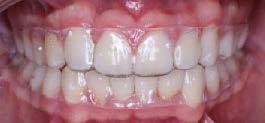

Estudios finales extraorales

En la fotografía de frente (Figura 11) se ve la sonrisa armónica, la corrección de la línea media dental superior e inferior respecto a la línea media facial, en la de perfil final (Figura 12) se mantuvo el perfil labial. El tiempo de tratamiento activo fue de 2 años y 3 meses.

Estudios intraorales finales

En la Figura 13 se muestra líneas medias dentales superior e inferior coincidentes, se obtuvo clase II molar funcional bilateral y clase I canina izquierda y derecha con el OD 14, la correcta adhesión del trasplante conformado como carilla en la cara vestibular del OD 13, oclusión funcional, overjet y overbite adecuados.

Se observa la liberación del apiñamiento superior e inferior, ( Figura 14) se incluyó el OD 13 al arco y se consiguió la forma oval de ambas arcadas.

En la radiografía panorámica (Figura 15) se ve el paralelismo radicular, 26 OD presentes, OD 18 y 28 en formación. En la retención del tratamiento se le colocaron al paciente (Figura 16) fijos de 3 a 3 y además utilizar termoformados superior e inferior.